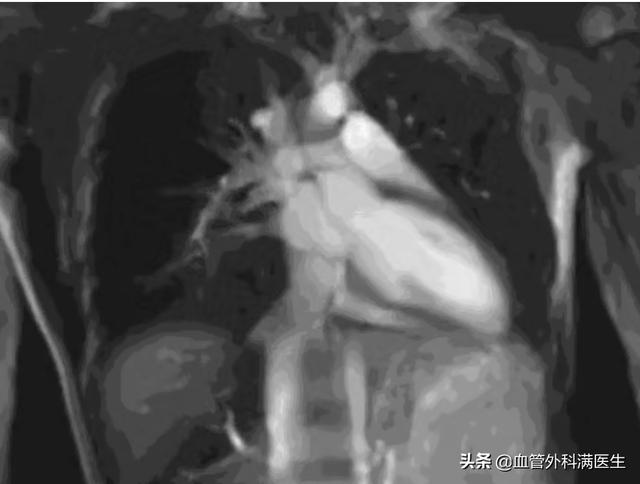

因为核磁主要采用的是电磁波原理,而电磁波所放射出来的量相当于平时手机及电视机所释放出来的量,对身体不会有害。